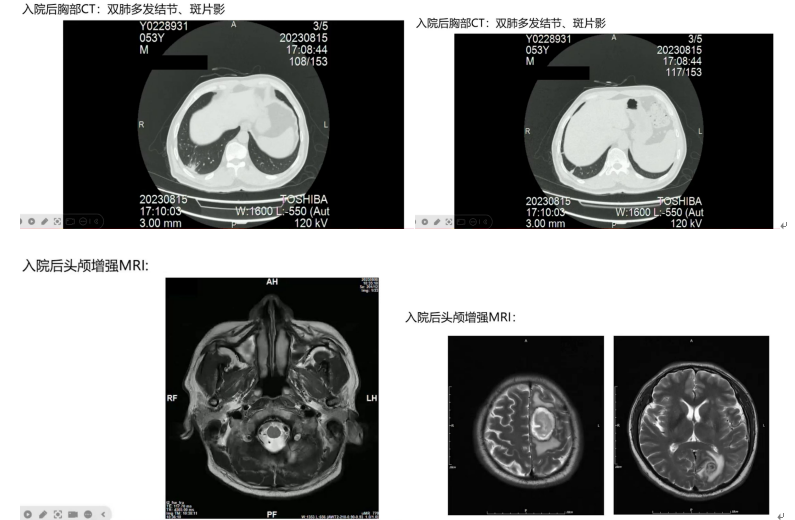

胸部CT显示双肺多发结节、斑片状影,右下肺空洞样病变较前实变;头颅增强MRI提示左侧额叶脑室多发脓肿病灶且脓肿壁强化;浅表淋巴结超声提示腹股沟和腋窝多发肿大淋巴结。